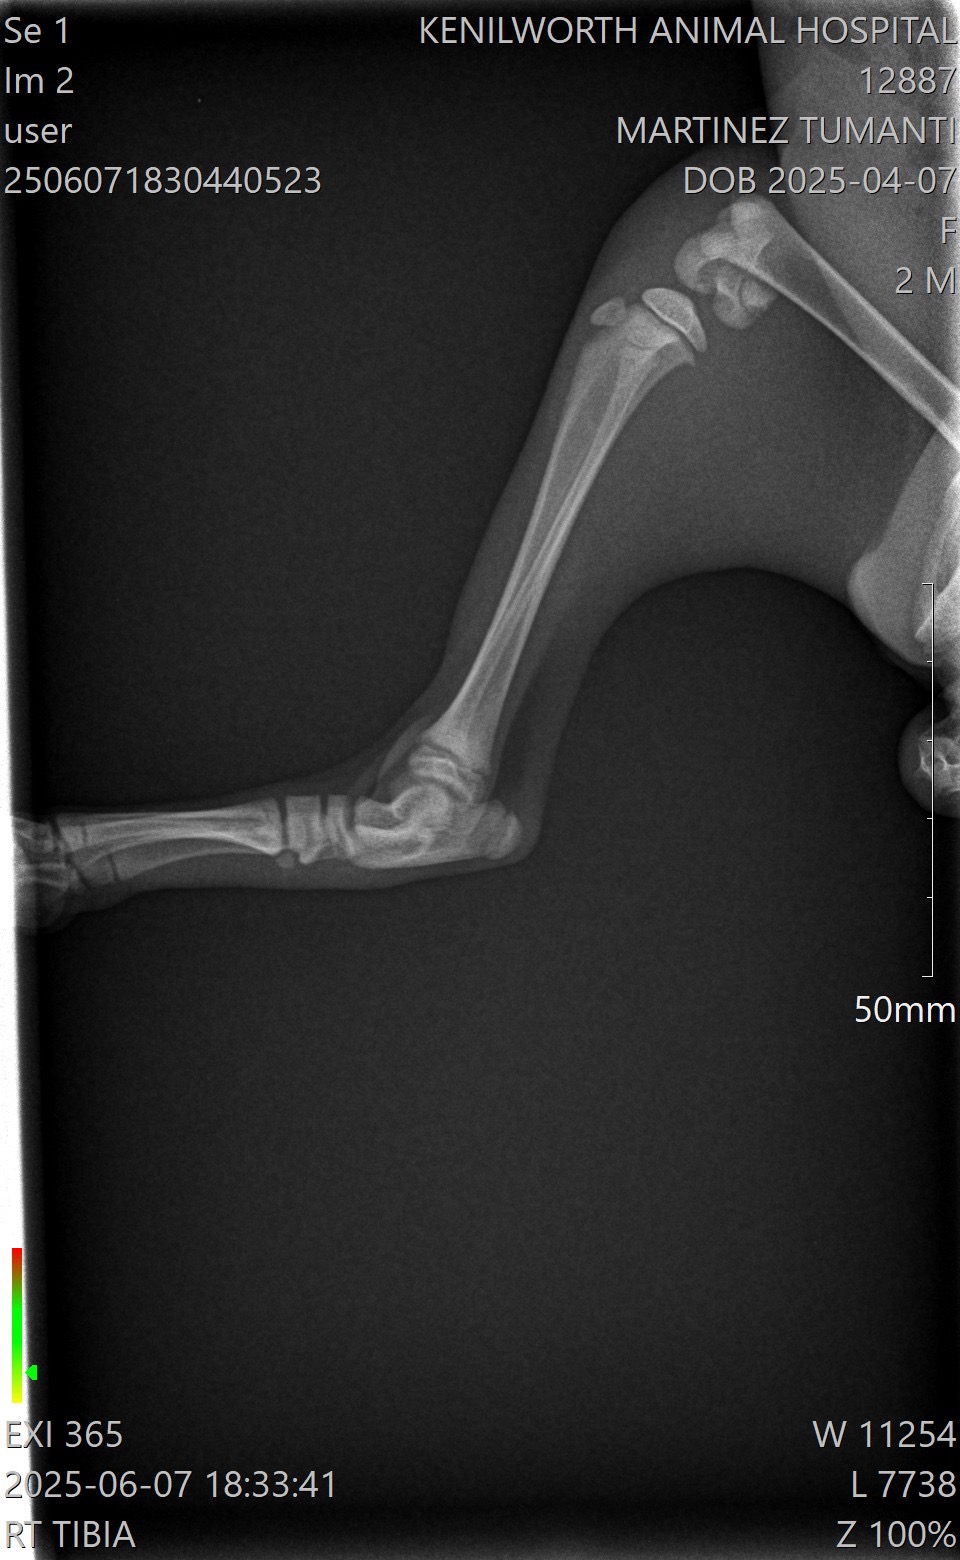

After many vet consults and visits, an orthopedic specialist at Eclipse Veterinary Hospital confirmed the dislocated hip and also found bilateral distal fractures in both of his hind legs. He will need surgical repair of the fractures, follow-up care, X-rays and pain management.